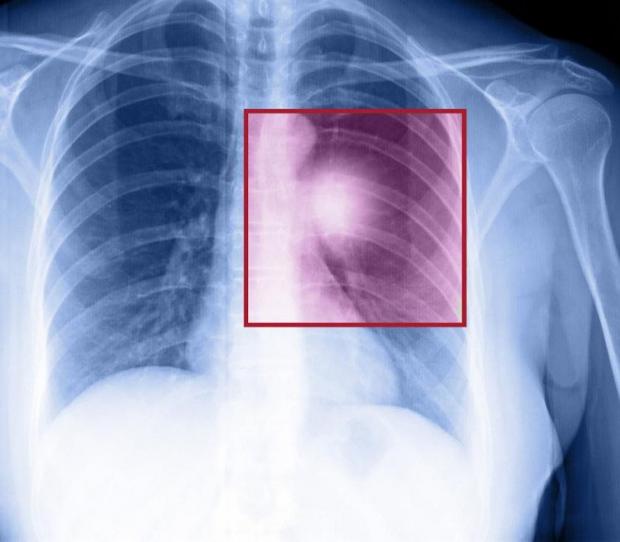

Ung thư phổi

Ung thư phổi là loại ung thư gây tỷ lệ tử vong cao hàng đầu tại các nước trên thế giới trong đó có cả các quốc gia có trình độ phát triển kinh tế – xã hội cao như Hoa Kỳ. Theo NCI, thuốc lá chính là thủ phạm chính gây nên căn bệnh này.

Ung thư phổi có hai loại chính là ung thư phổi không phải tế bào nhỏ và ung thư phổi tế bào nhỏ. Loại thứ nhất là loại phổ biến trên toàn cầu. Đối tượng mắc ung thư phổi là những người trong độ tuổi từ 55 đến 65 tuổi.